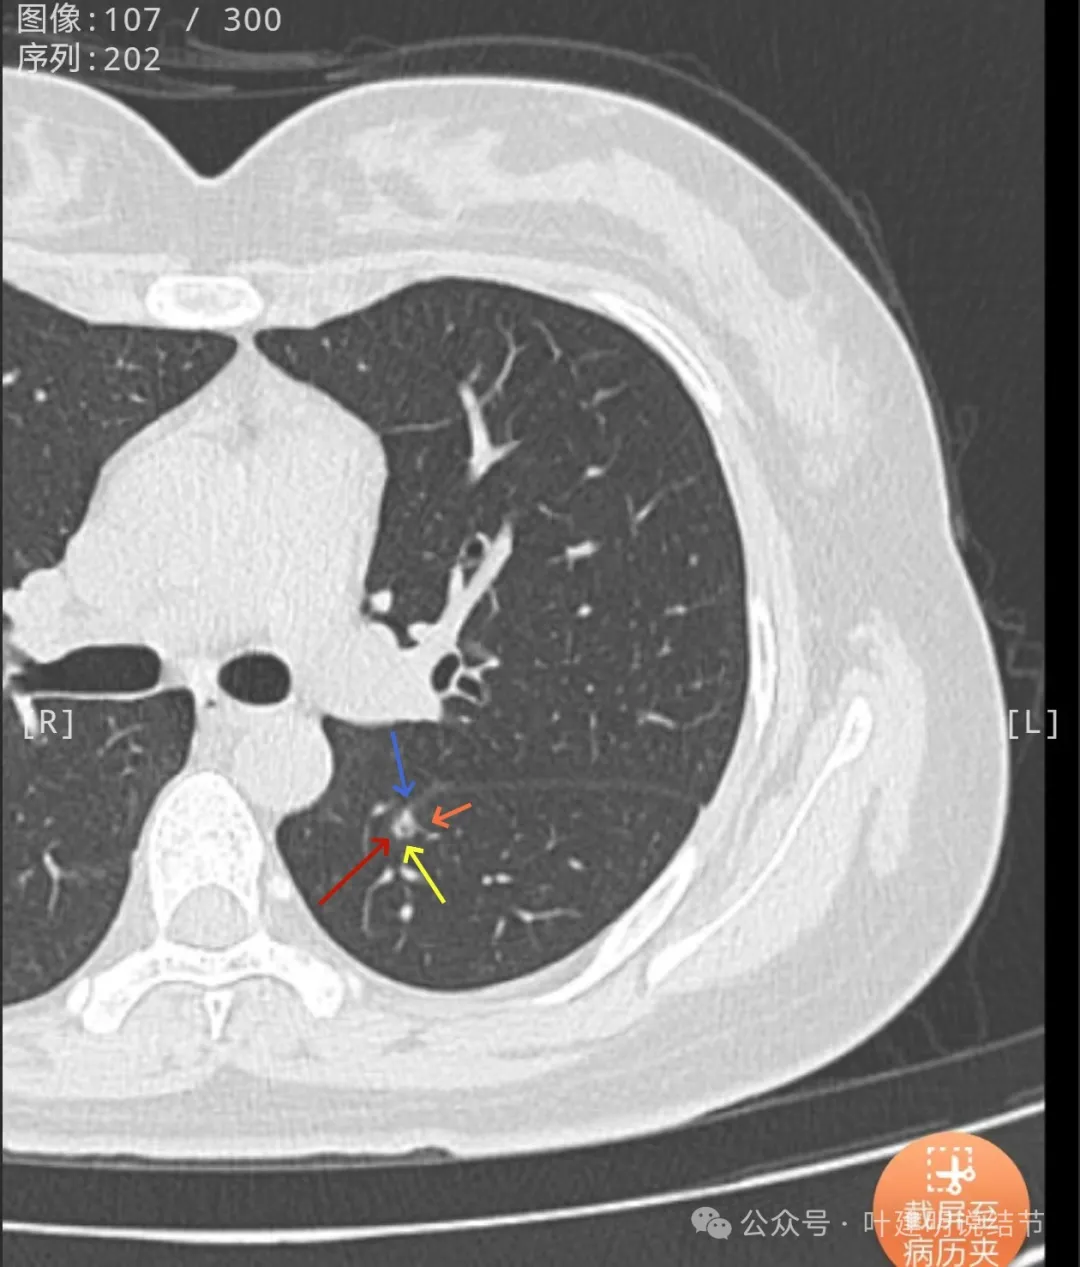

叶间裂有牵拉,有微小血管进入病灶,灶内有小空泡征,密度整体显得较高,轮廓清楚,瘤肺边界清。

表面有小棘突或毛刺样征,密度显得杂乱。

轮廓清,小空泡征明显,密度较高,基本上是实性。